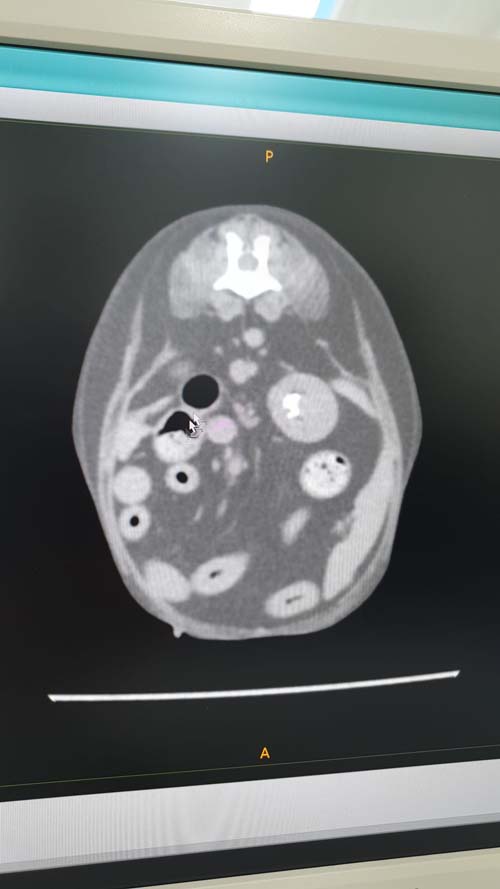

หลายๆ บ้าน ib มาถามผลการ CT Scan แชลมาล ขอบคุณมากนะคะ มาค่ะ มารีวิวเป็น Q&A ว่าทำไมต้องซีที มันจำเป็นมั้ย และทำยังไงบ้างนะคะ เนื้อหาเต็มๆ และยาวมากๆ อาจจะเครียดนิดนึงนะคะ ใครขี้เกียจอ่าน ข้ามไปดูคลิปได้เลยในคอมเม้นต์ค่ะ ขอบคุณน้องมาร์ช Marsh The Happy Dog ที่ให้ข้อมูล มาให้กำลังใจด้วย ช่วยถ่ายคลิปให้ แถมแจกขนมจากเจอร์ไฮปลอบใจอีกต่างหาก เลิฟ Q1: ทำไมคิดมาทำ CT Scan A1: แชลมาล มีอาการไม่สบายตัว เหมือนจะเจ็บ หรือปวด เล็กๆ ไม่ที่หลังก็ท้อง อาการคือ เวลากินเสร็จ จะตัวสั่น ประมาณ 5 นาทีก็หาย ไม่ยอมเดิน ไม่ยอมยกขาหน้า ไม่ขึ้นสเต็ปเตี้ยๆ ที่เคยขึ้น แต่ไม่มีการเกร็งตัว, โก่งตัว และยังวิ่งเล่น เห่า กิน ถ่ายปกติ เป็นประมาณ 2-3 วันก็หายปกติ แล้วอีกเดือนมาเป็นใหม่ พาไปหาหมอ หมอ 3 คนบอกว่าเป็นปวดหลัง อาจจะจากกระดูกงอก หรือกระดูกทับเส้น ตามวัย อีกคนบอกว่าอาจจะปวดท้อง ถ้าจะให้รู้แน่ๆ ก็ต้องทำ CT Scan จะได้ดูทั้งหลังและท้องในทีเดียว Q2: CT Scan ต่างจาก X-Ray ยังไง A2: เป็นการใช้รังสี X ในการสแกน เหมือนกัน แต่ซีที ทำได้ละเอียดและครอบคลุมมากกว่า สามารถจำลองภาพเป็น 3 มิติให้เห็นพื้นผิวได้ชัดกว่า ทำทีเดียวได้ทั้งร่าง ทุกส่วน ทุกอวัยวะ ถ้า เอ็กซ์เรย์ จะถ่ายได้ทีละส่วน Q3: ทำไมเลือกทำที่ Crystal CT Scan Center A3: การทำซีที คือการต้องนอนให้นิ่งที่สุด เพื่อเวลาสแกน จะเห็นภาพได้ชัด ถ้าหากมีการสั่น ขยับ เคลื่อนไหว ภาพที่ได้จะเบลอๆ เป็นควัน ทำให้วิเคราะห์ผลยาก และอาจจะคลาดเคลื่อน ในปัจจุบัน สำหรับสัตว์ เลยต้องวางยาสลบ ซึ่งแชลมาลมีภาวะโรคหัวใจ เสี่ยงกับการวางยาสลบ แล้วจะไม่ฟื้น ที่ Crystal CT Scan Center เค้าเป็นเครื่องแบบใหม่ ที่มี 128 สไลด์ (จำนวนสไลด์ ยิ่งมาก เครื่องจะยิ่งทำงานได้เร็ว) ทำให้แค่วางยาซึม ไม่ต้องวางยาสลบ เราเลยเลือกที่นี่ค่ะ (ตอนที่สแกน ถามเจ้าหน้าที่ของ บ.เครื่องที่อยู่ด้วย เค้าบอกว่า สำหรับ รพ.ส. ตอนนี้ยังมีแค่ที่นี่ที่เดียว ที่ใช้เครื่องรุ่นนี้ค่ะ) Q4: ทำยังไงบ้าง เห็นอะไรบ้าง A4: ตอนแรกก็คุยกับคุณหมอก่อนว่า เรามีอาการยังไงมา อยากตรวจอะไร คุณหมอแนะนำยังไงบ้าง แชลมาลกับชมิล มีคุณหมอประจำอยู่ 3 ที่ คือที่ รักษาทั่วไป ที่คริสตัลเพ็ท รักษาตา และฉุกเฉินตอนกลางคืน ที่รัตนาธิเบศร์ สาขาเกษตร-นวมินทร์ รักษาหัวใจ ที่ ประศุอาทร มหิดล ถ้าไม่ได้เป็นคนไข้ที่คริสตัลเพ็ท ก็มาสแกนได้นะคะ ไม่จำเป็นต้องเป็นคนไข้ที่ คริสตัลเพ็ทเท่านั้นค่ะ ของเคสแชล คุณหมอบอกอยากสแกน หัว คอ หลัง ปกติถ้าสแกน 1 จุด ราคา 3,500 บาท สแกนทั้งตัว ราคา 5,500 บาท ถ้าจะดู 3 จุด ก็สแกนทั้งตัวไปเลย แป๊บเดียว ตัวจิ๋วเดียว คุณหมอให้ลองไปนั่งที่เครื่องแล้วเลื่อนไปมา ว่าไหวมั้ยถ้าไม่วางยา แต่แชลผู้ซึ่งสั่นตลอดเวลา มิไหว เลยวางยาซึมไปค่ะ เพิ่มค่าวางยาซึม 1,000 บาท พอยาซึมเริ่มออกฤทธิ์ ก็พาไปนอนที่เครื่อง มีพี่ๆผู้ช่วยจับ และเริ่มสแกน แป๊บเดียวมากๆ ไม่ถึง 10 นาทีก็เสร็จ ก็ออกมานั่งรอน้ำลายไหลเพราะฤทธิ์ยา แชลใช้เวลาขับยาออกจากตัวค่อนข้างนาน ประมาณ 3 ชม. เพื่อนๆที่เค้าเข้าไปทีหลัง ออกมาก็กินข้าวได้เลยค่ะ การฟื้นจากยา จะแล้วแต่ตัวค่ะ รอคุณหมอเช็คฟิล์ม ตัดเซฟใส่ DVD ให้เรา (ฟรี) ถ้าใครมี USB Drive พกไปด้วยนะคะ คุณหมอเซฟใส่ให้ค่ะ และมีส่งรูปสำคัญๆ ในไลน์ให้ด้วยค่ะ Q5: ผลสแกนเป็นยังไงบ้าง A5: ตอนเข้าไปฟังผล คุณหมอเปิดให้ดูเป็นภาพไล่ไปเรื่อยๆ มันจะเหมือนเราค่อยๆเข้าไปในตัวแชลมาลเลยค่ะ ใช้เวลาตรงนี้เกือบ 50 นาทีแหนะค่ะ ขอบคุณคุณหมอมากๆ ที่อธิบายละเอียดมากเลย ก็ไล่ตั้งแต่ รูจมูก เข้าไปในตา กะโหลก หู หลอดลม ปอด หัวใจ ไล่ไประบบทางเดินอาหาร จนถึงมดลูก เห็นกระทั่งตอที่ผูกปิดมดลูกตอนทำหมัน และมาที่กระดูก ซี่โครง ดูช่องว่างระหว่างกระดูก ดูการเสื่อมของกระดูก ดูสะบ้า สะโพก ว่าอยู่ในตำแหน่งดีมั้ย มีเคลื่อน มีอะไรมั้ย ครบเลยค่ะ แชลมาล กระดูกดีมากๆ ทุกอย่างสวยงาม แต่มีเจอ ภาวะน้ำในสมอง และกะโหลกไม่ปิด ถ้าหมอจับคลำ ทุกคนจะบอกว่ากะโหลกปิดค่ะ แต่เพราะสแกนเลยรู้ว่าไม่ปิด และต้องระวังเรื่องการชัก และกระแทกแรงๆ ตะกอนในถุงน้ำดี ต้องเลี่ยงกินมัน งดอาหารที่มีไขมันสูง มาดูสูตรอาหารใหม่ และมีนิ่วในไต ซึ่งคิดว่าเป็นสาเหตุที่ทำให้ปวดค่ะ อาจจะเกร็งไต แล้วมันเลยไปแสดงออกว่าไม่สบายตัว สแกนรอบเดียว เจอ 3 โรคต้องเฝ้าระวัง Q6: ทำไมมีนิ่วในไต แต่ค่าเลือดปกติมาก A6: แชลมาลเพิ่งตรวจเลือดไปตอนสิงหา และตุลา ค่าเลือด ปกติดีทุกตัวค่ะ คุณหมออธิบายว่า ถ้าปกติตรวจเลือดแล้วค่าไตปกติ ไม่สูง หมอจะไม่สั่งตรวจค่าฟอสฟอรัส ค่าการทำงานของไตต่อ เพราะมันยังไม่จำเป็นที่ต้องดู แต่ในกรณีนี้คือ เจอนิ่วจากการสแกน ไตอาจจะยังไม่ส่งผลว่ามีปัญหา แต่เจอเร็ว ก็ต้องตรวจเลือดเพื่อดูค่าฟอสฟอรัส และเช็คฉี่ ว่าเป็นนิ่วประเภทไหน เพื่อรักษากันต่อไปค่ะ Q7: มันดีมั้ย ควรทำมั้ย A7: จากที่ทำมา รู้สึกประทับใจมากค่ะ เพราะหมาพูดไม่ได้ เค้าบอกเราไม่ได้ว่าเค้าเจ็บตรงไหน เจ็บแบบไหน ต้องใช้การสังเกตล้วนๆ การที่สแกนเข้าไปให้เห็นภาพเลย มันก็ตอบเราได้ดี ไม่ต้องมานั่งเดาเอง หยกยังคิดว่า ถ้าเราสแกนปีละครั้งเพื่อเป็นการเช็คร่างกายใหญ่ พร้อมตรวจเลือดด้วย ก็น่าจะดีนะคะ รู้ก่อน รักษาก็ง่ายกว่า เร็วกว่า Q8: เคลมประกันได้มั้ย A8: คุณหมอบอกว่าสามารถเคลมได้ค่ะ แต่แชลมาลอายุเกินทำประกันแล้ว เลยจ่ายเต็ม รอบนี้จ่ายไป 6,500 บาทถ้วน ได้ความโล่งอกว่าเราไม่ได้คิดไปเองว่าหมาเราปวดท้อง (ทั้งๆที่ไม่โก่งตัว) และจะได้รักษาได้เร็ว เพื่อคุณภาพชีวิตที่ดีของเด็กๆ ค่ะ มีคลิปผลการสแกนอยู่ในคอมเม้นต์นะคะติดต่อสอบถามนัดหมาย @CrystalCTscan